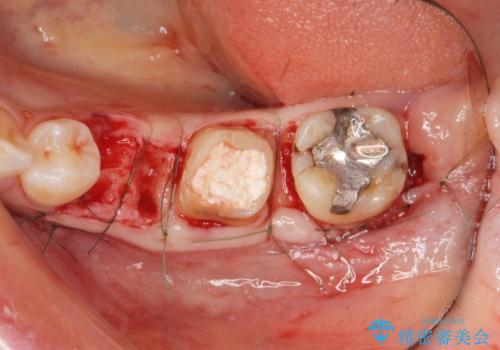

ブリッジ治療の予知性を高めるために、虫歯の徹底的な除去に加え縁上歯質を確保するための歯周外科手術、マイクロスコープを用いた精密根管治療を行う治療計画としました。

- 26万円(仮歯・ファイバーコア・フルジルコニアクラウン×3) 費用は治療当時の料金となります

外科処置の注意事項(リスク・副作用など)

- 外科手術のため、術後に出血、痛みや腫れ、違和感を伴います

- 口腔内の状態によっては適応できないことがあります